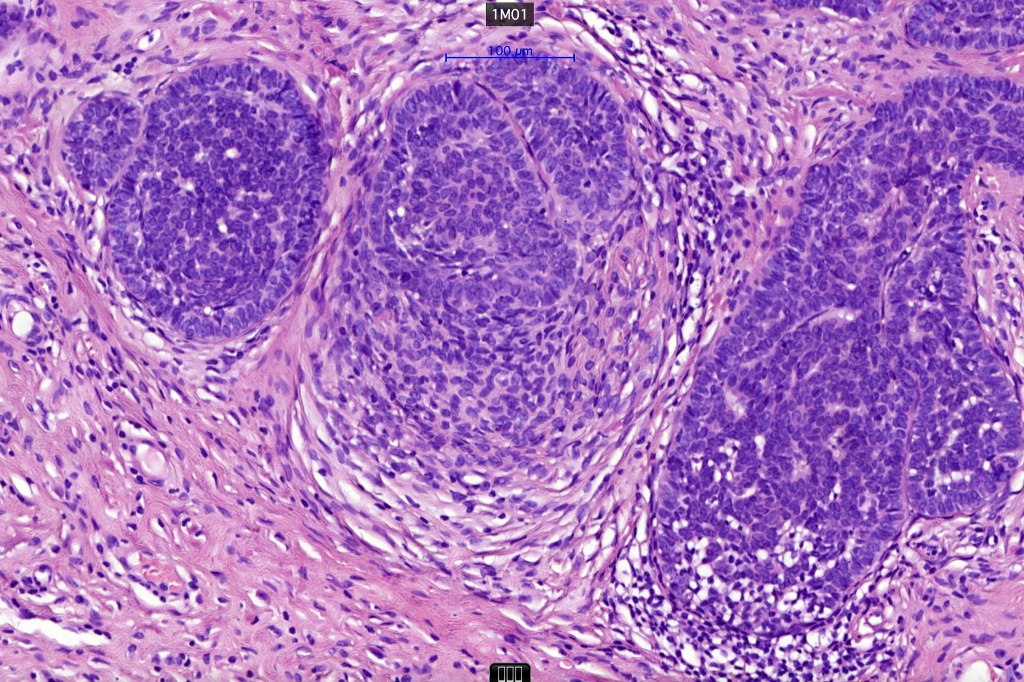

•The classical appearance consists of keratocysts & lobules of basaloid cells

•Basaloid lobules show peripheral palisading

•Perifollicular mesenchyme is always conspicuous and sometimes densely aggregated are seen indenting the baslaloid lobules (papillary mesenchymal bodies)

•Narrow epithelial strands arising from the basaloid lobules are often present

Trichoepithelioma should be distinguished from trichoblastoma since the latter is very rarely syndromic. Trichoepithelioma is largely a dermal tumor whereas trichoblastoma often extends from the dermis into subcutaneous fat or deeper in very large examples. Papillary mesenchymal bodies are much better formed and generally more obvious in trichoepithelioma. Trichoepithelioma must also be distinguished from basal cell carcinoma. Retraction artifact & stromal mucin are features of basal cell carcinoma and not trichoepithelioma. Papillary mesenchymal bodies are not seen in basal cell carcinoma.